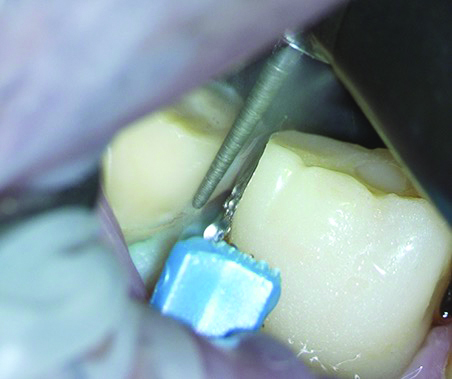

To begin the tooth preparation, depth cuts were made first on the vestibular aspect and then on the distal and occlusal areas using a depth indicator bur (Figure 3). These cuts were then marked with a pencil to ensure a minimally invasive preparation of 1 mm (Figure 4). Next, the grooves were connected around the entire tooth structure using a round-end diamond bur (Figure 5). The rounded shoulder margin was then defined on the vestibular aspect based on the previously marked finish line, extending distally while maintaining a 0.5-mm depth coronally. Under full microscopic control, the clinician carefully broke the proximal contact while a wedge-matrix combination was used to protect the adjacent tooth (Figure 6).

Fig 3. Preparation of the tooth began with the use of a depth indicator bur, first on the vestibular, then on the distal and coronal aspects.

Figure 3

Fig 6. After the rounded shoulder margins were defined, the approximal contact was broken, with a wedge-matrix combination protecting the adjacent tooth. This was done under full microscopic control.

Figure 6